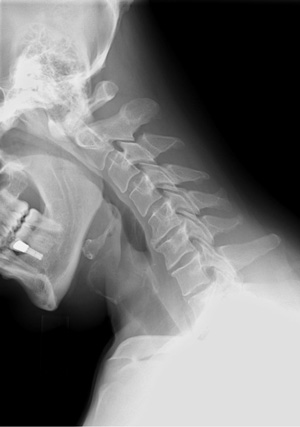

Pathologists commonly use radiographs when performing autopsies. The images can help them identify elements that may be questionable and then allows them to further investigate.

As the radiologic sciences have advanced over the years to include MRI's, CT's, and ultrasound, the accuracy has increased to a much greater degree and has made it even more relevant for gathering evidence within accident or crime scenes.